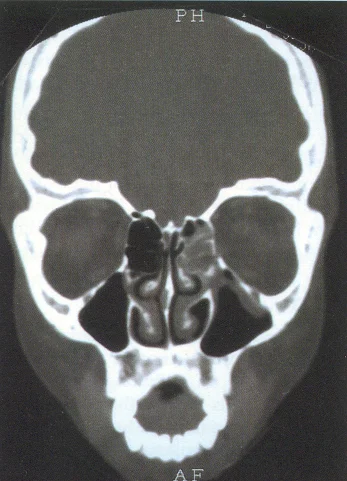

Floor Fractures

Orbital Fractures

Find the Fracture